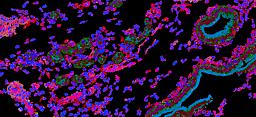

Pancreatic ductal adenocarcinoma is a lethal disease with limited treatment options and poor survival. We studied 83 spatial samples from 31 patients (11 treatment-naïve and 20 treated) using single-cell/nucleus RNA sequencing, bulk-proteogenomics, spatial transcriptomics and cellular imaging. Subpopulations of tumor cells exhibited signatures of proliferation, KRAS signaling, cell stress and epithelial-to-mesenchymal transition. Mapping mutations and copy number events distinguished tumor populations from normal and transitional cells, including acinar-to-ductal metaplasia and pancreatic intraepithelial neoplasia. Pathology-assisted deconvolution of spatial transcriptomic data identified tumor and transitional subpopulations with distinct histological features. We showed coordinated expression of TIGIT in exhausted and regulatory T cells and Nectin in tumor cells. Chemo-resistant samples contain a threefold enrichment of inflammatory cancer-associated fibroblasts that upregulate metallothioneins. Our study reveals a deeper understanding of the intricate substructure of pancreatic ductal adenocarcinoma tumors that could help improve therapy for patients with this disease.